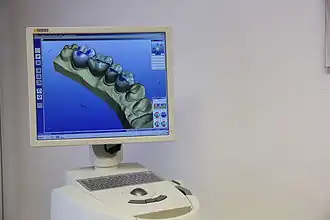

Im November 1895 entdeckte Wilhelm Conrad Röntgen die später nach ihm benannten Röntgenstrahlen, die die Untersuchung des Kiefers vereinfachten. Als Mittel zur örtlichen Betäubung von Zahnschmerzen wurde im Jahre 1905 das Lokalanästhetikum Procain von den deutschen Chemikern Alfred Einhorn und Emil Uhlfelder entwickelt, die dem Wirkstoff den Namen Novocain (lateinische Wortschöpfung für „Neues Cocain“) zuordneten. Damit waren die Grundlagen für eine moderne Diagnostik und Therapie gelegt. Die Zahnheilkunde erlebte daraufhin einen rasanten Fortschritt: von der Entwicklung zahlreicher oralchirurgischer Verfahren bis zur Anfertigung von Zahnersatz mittels CAD/CAM-Verfahren. Parallel zum Fortschritt der wissenschaftlichen Zahnheilkunde entwickelte sich das Berufsbild, was in der Geschichte des Zahnarztberufs dargestellt wird. Daneben entwickelte sich die Tierzahnheilkunde, die sich entsprechend modifizierter Verfahren der allgemeinen Zahnheilkunde bedient.